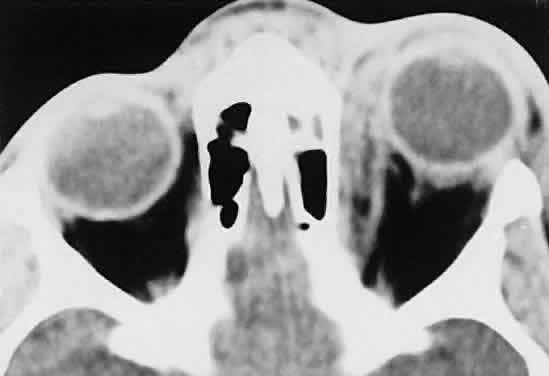

Acute blood cyst formation in this age group makes the distinction between a pre-existent but clinically silent lymphangioma and a rapidly emerging rhabdomyosarcoma a common orbital diagnostic problem. Evidence suggesting an orbitallymphangioma includes the variable finding of conjunctival or eyelid components of the malformation.86 Conjunctival lesions appear as ectatic channels filled with clear or hemorrhagic fluid. Eyelid ecchymosis may result from the seepage of blood out of the thin-walled orbital cysts. Additional developmental anomalies of the eye and adnexa may be present. Other head and neck involvement may be manifest as local hypertrophy (e.g., of the cheek or lips), and cystic palatal lesions may be seen. CT discloses a single or multilobulated mass, which represents only the blood cyst portion of the tumor (Fig. 14). Individual lobules may have different radiodensities depending on the presence of clots or liquefied blood within each cyst (Fig. 15). A generalized increase in orbital dimensions suggests a long-standing, probably congenital process. Echography may help differentiate the cystic components of lymphangioma from cellular rhabdomyosarcoma. Echography shows the blood cysts to be acoustically inactive spaces, with extremely low internal reflectivity (Fig. 16). Clots within the cysts can increase internal heterogeneity, however. MRI has virtually eliminated the need for diagnostic biopsy in this condition, because of its ability to show differing magnetic properties of suspended, degrading blood products (Fig. 17).